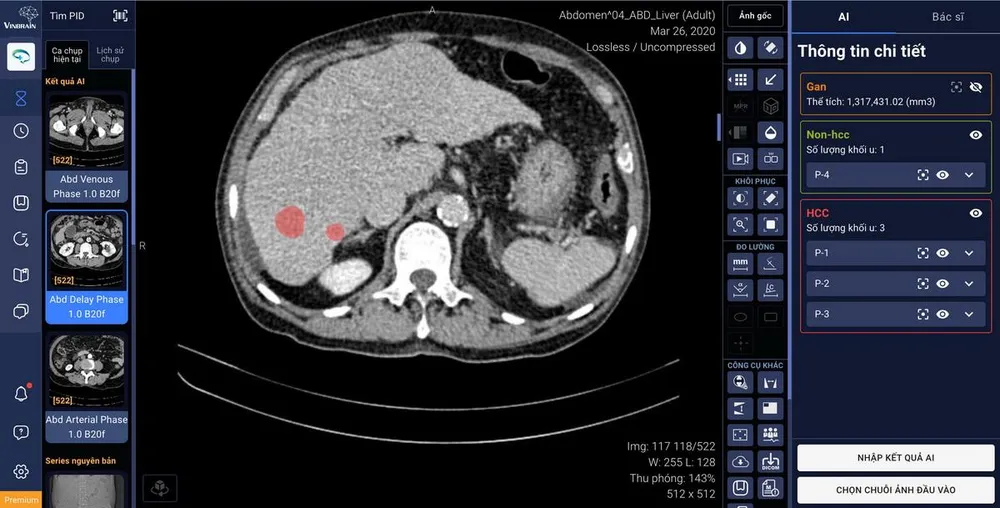

Tính năng mới của phần mềm DrAid sẽ tự động khoanh vùng và phân loại tổn thương gan bằng ứng dụng trí tuệ nhân tạo, kết nối trực tiếp với PACS (hệ thống lưu trữ và truyền tải hình ảnh y tế) và trả về trên phần mềm kết quả AI khoanh vùng của gan và các tổn thương cũng như phân loại các loại tổn thương.

DrAid hỗ trợ tính năng tự động khoanh vùng và phân loại tổn thương gan ứng dụng trí tuệ nhân tạo, kết nối trực tiếp với phần mềm quản lý hình ảnh của bệnh viện (PACS) |